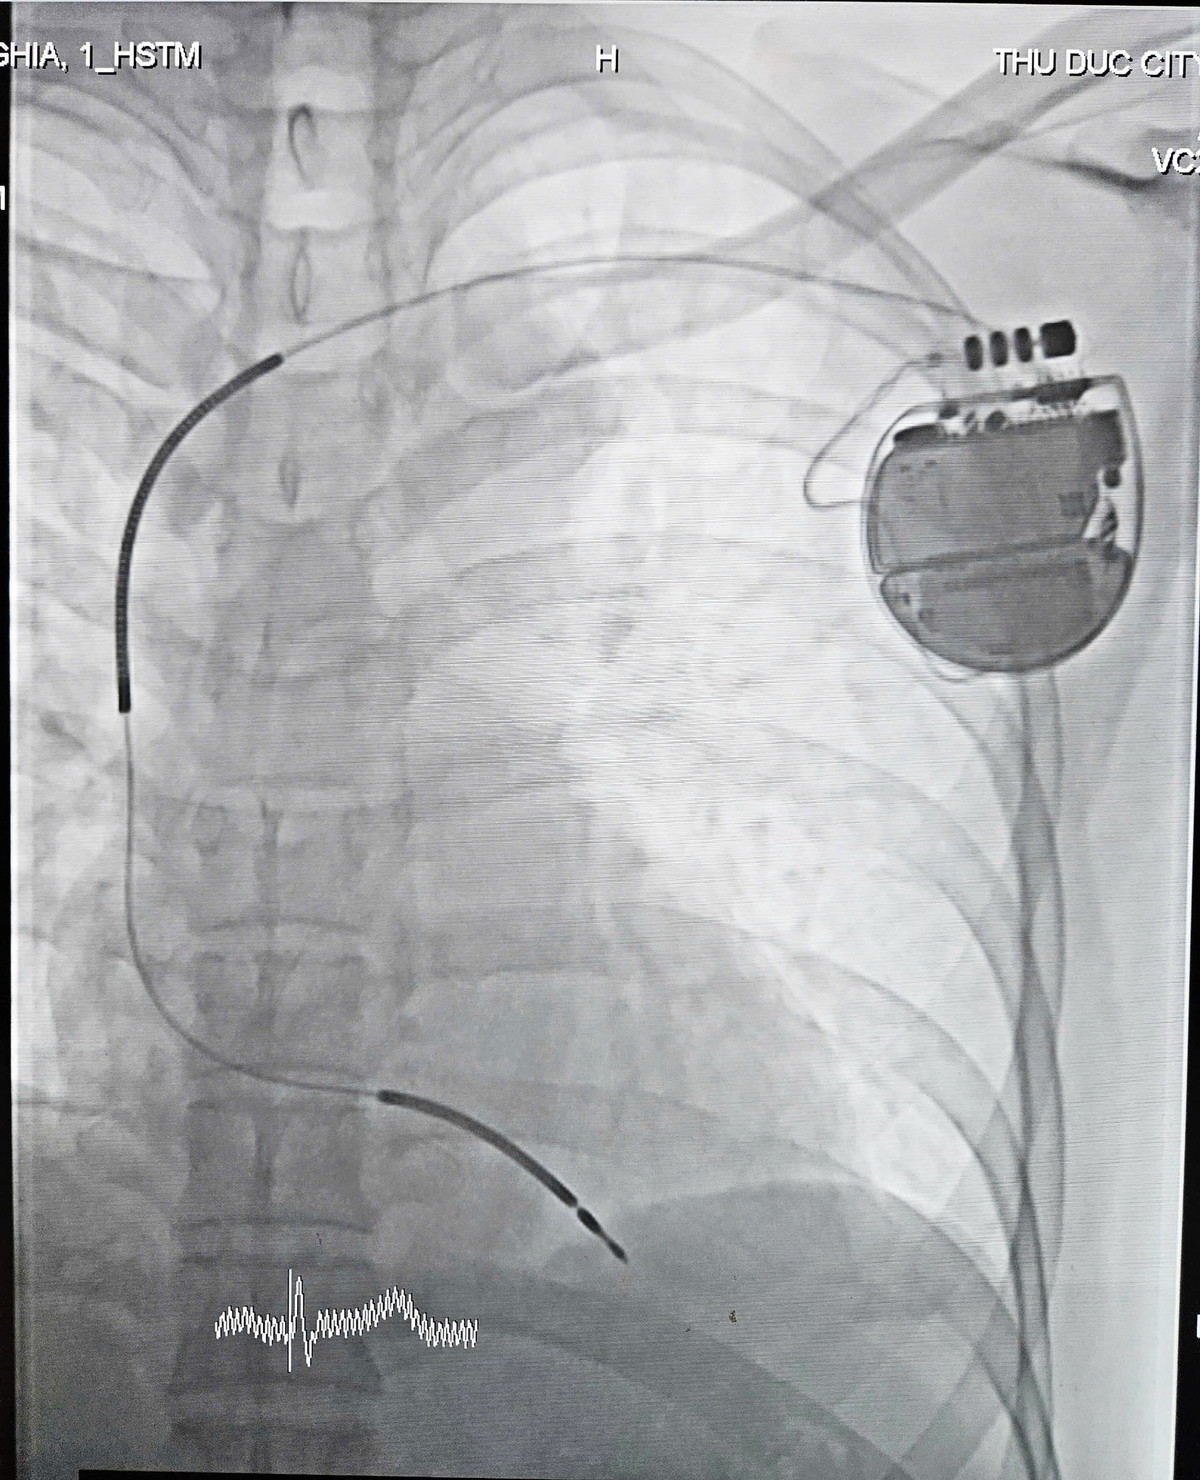

Thực hiện cấy máy nhịp tim - Ảnh BVCC

Sau khi hồi phục, ê-kíp Nhịp tim thuộc khoa Hồi sức Tim mạch, dưới sự cố vấn chuyên môn của TS.BS Phạm Hữu Văn, Phó chủ tịch Hội Nhịp tim học Việt Nam, bệnh nhân được tiến hành cấy máy khử rung tự động ICD - một thiết bị có khả năng phát hiện và xử lý các rối loạn nhịp nguy hiểm.

BS Nguyễn Phúc Nguyên cho biết, máy phá rung ICD là thiết bị điện tử nhỏ được cấy dưới da vùng ngực và kết nối với tim qua các dây điện cực. Thiết bị có tuổi thọ từ 7-10 năm và sẽ được thay mới khi hết pin. Máy hoạt động 24/7 để theo dõi nhịp tim, đồng thời có khả năng phát hiện, điều trị và ngăn ngừa các cơn rối loạn nhịp thất nguy hiểm như rung thất và nhịp nhanh thất.